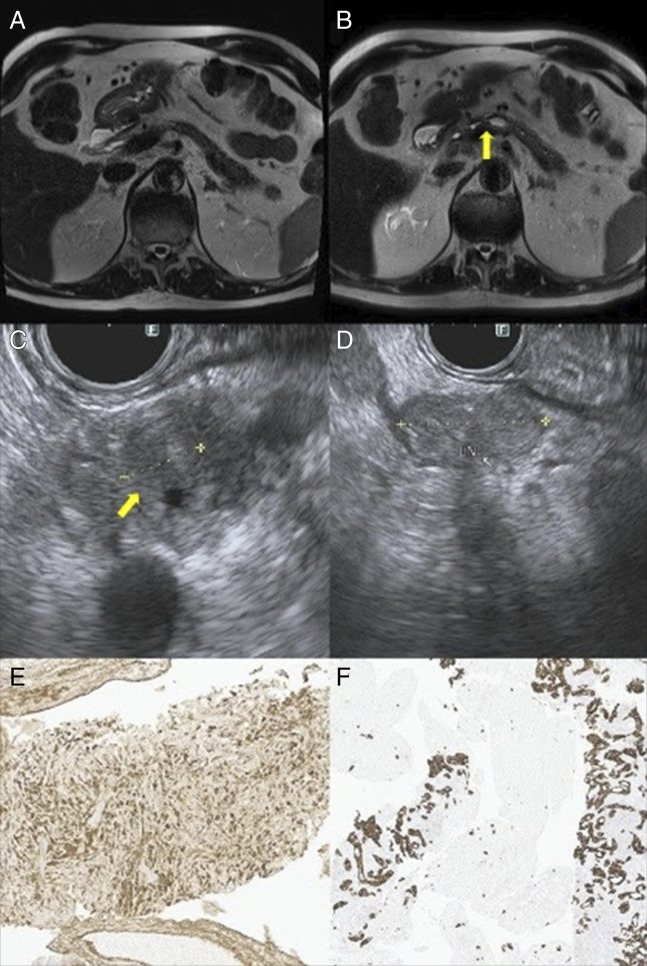

Autoimmune pancreatitis (AIP) and pancreatic cancer share clinical and radiological features, making biopsy the only definitive way of differentiating them. Numerous reports in the literature describe the co-occurrence of AIP and pancreatic cancer either in a synchronous manner or metachronous manner raising the question of which condition predisposes to the other and whether a causal relationship exists between them. Studies suggest shared mechanisms, including K-ras mutations and tumor suppressor gene silencing. This case highlights the importance of long-term surveillance in AIP patients to monitor for malignancy.